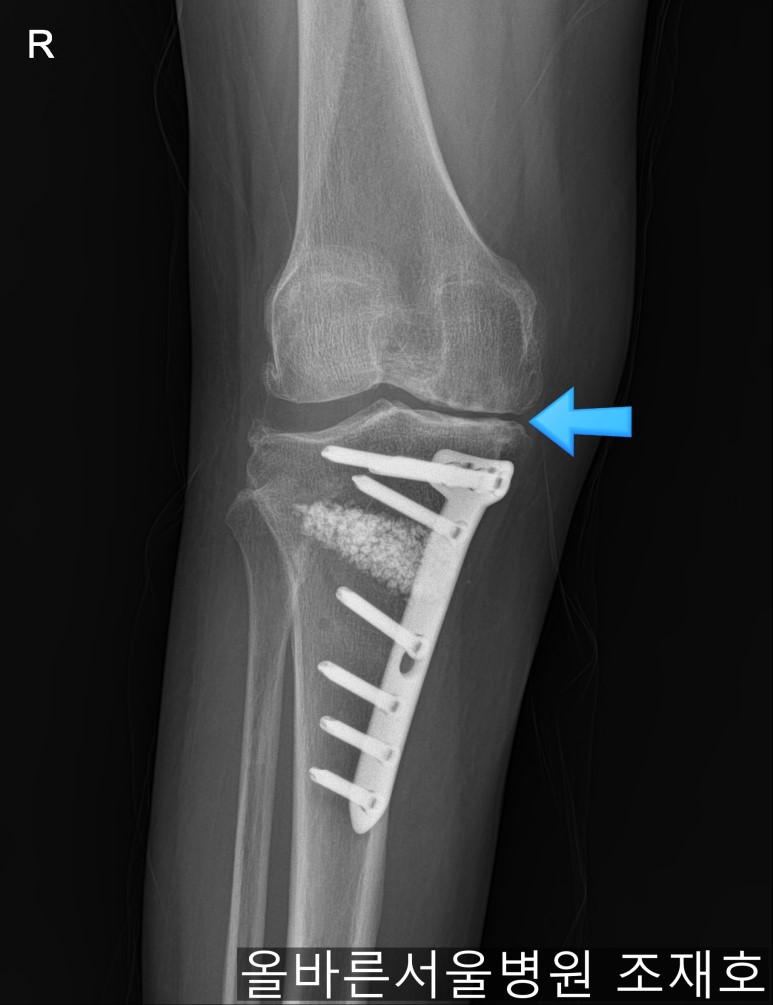

仅通过放射线片子观察到:右膝由于炎症严重,内侧胫骨及股骨已接触在一起,向内测严重变形。

如果通过X光片也观察到相同的病症,可以判断内侧关节的软骨大部分都损伤了。

观察膝盖下肢排列的扫描图像可看到右腿严重变形,身体中心向内倾斜。

手术后可通过片子看到矫正后的正面样子。

此时内侧稍微分开,开始行走且软骨开始再生,内侧会更加分开。

侧面也矫正成功。